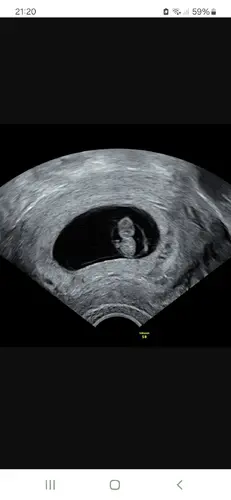

Hallo zusammen, bei meinem ersten Termin im Juli konnte man nur Höhle und Dottersack sehen. 2 Wochen dann den kleinen Zwerg (guckt mal, es winkt 🤭). Am 30.08 haben wir dann den NIPT.